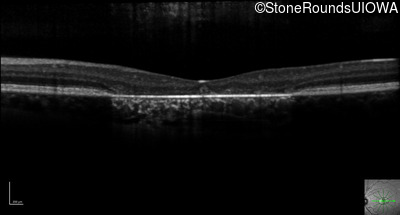

Optical Coherence Tomography - Left - 20/25 -1 sc

Exemplar / OCT Stack